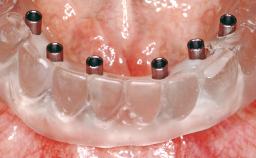

An 83-year-old male patient requested treatment for his existing maxillary complete overdenture and mandibular complete denture. He reported no general medical conditions of significance that would affect his dental treatment and was taking no prescription medication. He denied suffering from oral pain and displayed no evidence of parafunctional habits or temporomandibular joint disorder. Oral and radiographic evaluation revealed two retained maxillary teeth (13 and 15) supporting prefabricated ballshaped attachments. Both teeth were mobile and associated with active periodontal disease and extensive dental caries; these were considered non-restorable and were recommended for extraction. The patient’s existing complete maxillary and mandibular prostheses were approximately 2 years old. He was very satisfied with the appearance of both prostheses. His chief complaint was related to the instability and lack of retention associated with the existing mandibular prosthesis.

# of Implants | 2 |

Attachment | Reduced-Diameter|Two-Piece |